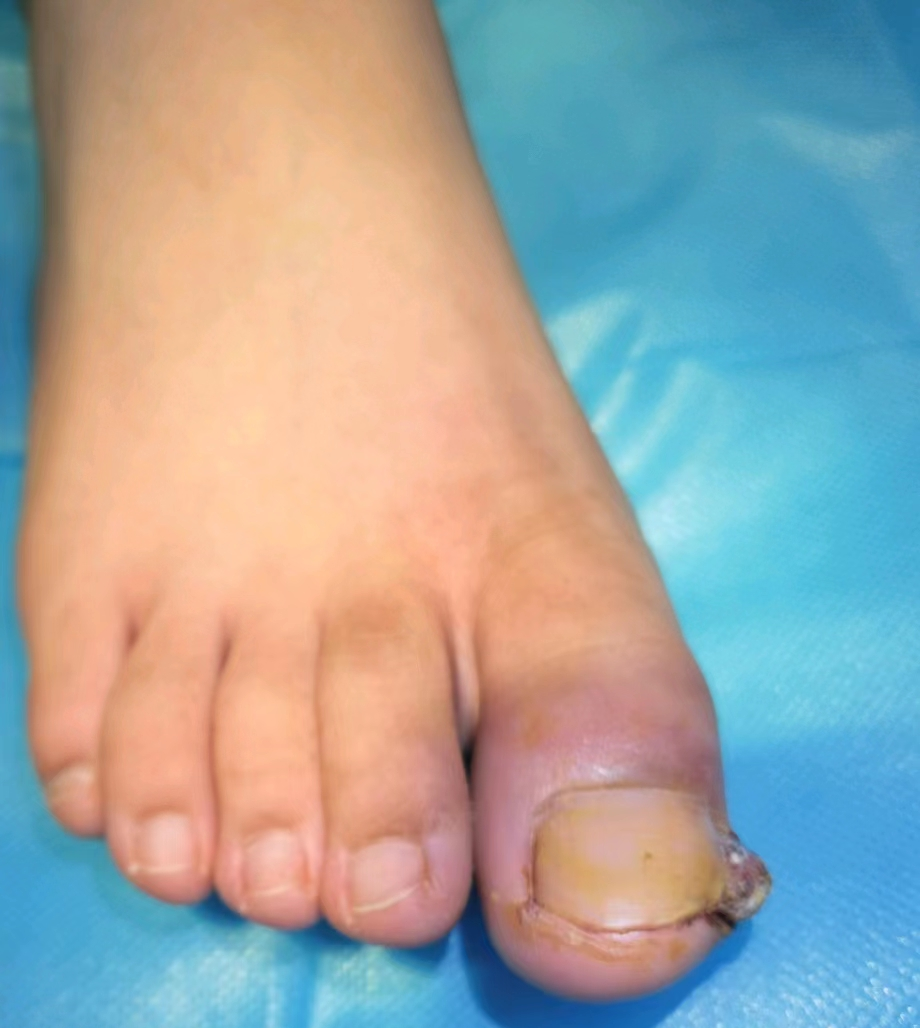

慢性甲沟炎,顾名思义,就是甲沟反反复复发炎,脚趾好不了几天,又肿了。就像下面的脚趾,内侧缘甲沟炎,导致了整个脚趾肿胀。

而局部反复发炎,会导致肉芽组织增生,就像下图箭头指向的部位。